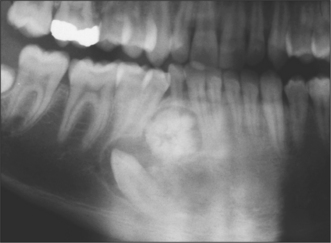

Ameloblastomas

These are the most common of the odontogenic tumours with many, including malignant, variants (see pathology texts for subclassification). They almost always present as a radiolucency (Fig. 8.7), often at the angle of the mandible and can, in some instances, be confused with the odontogenic keratocyst or dentigerous cyst. When they are small they can be unilocular but large lesions usually take on a multilocular appearance with a less well-defined border. Resorption of cortical bone and roots of adjacent teeth are common findings. Interestingly, despite the moderately aggressive growth pattern of these tumours, they rarely cause damage to the neurovascular bundle, in the mandible. They tend to displace it as they enlarge, so that numbness of mental nerve distribution is a rare clinical feature compared with osteogenic malignancy or intraosseous secondary malignancies.

image

Fig. 8.7 Ameloblastoma.

The most appropriate treatment is to resect the tumour with a margin of surrounding bone. For the ameloblastic fibroma conservative excision and for the unicystic ameloblastoma, enucleation alone may provide adequate treatment, but as with all this group, radiographic follow-up should be maintained for an indefinite period.